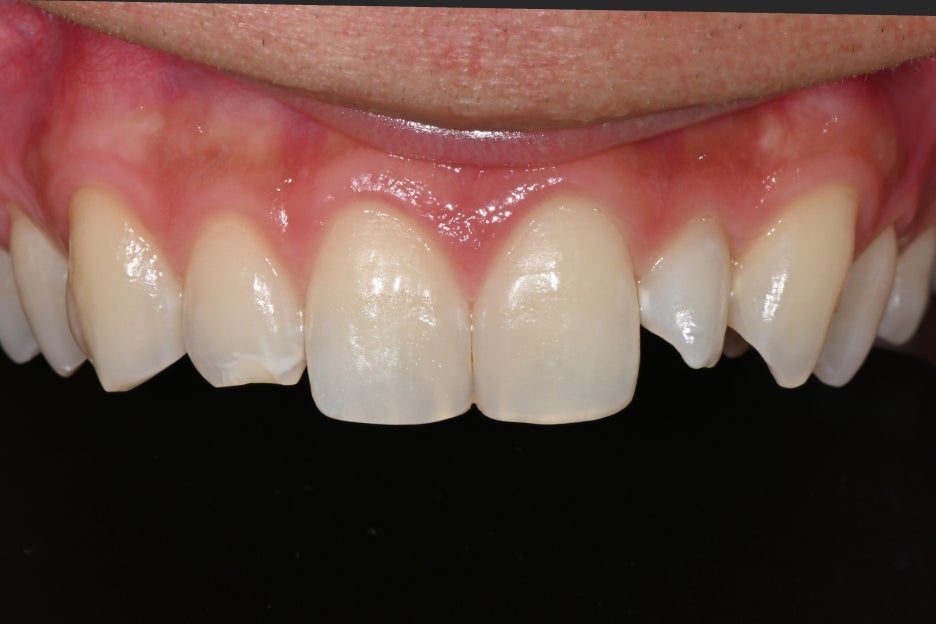

After finding and correcting the most natural volume for both teeth,

final bonding was performed.

Object Zero Laminate bonding

- Creating naturally looking front teeth

The final bonding was performed using materials whose strength and stability have been verified.

<After bonding>

Right after placement, the patient said,

It looks so natural, as if they were my original teeth, and not obvious at all.

They were very satisfied.